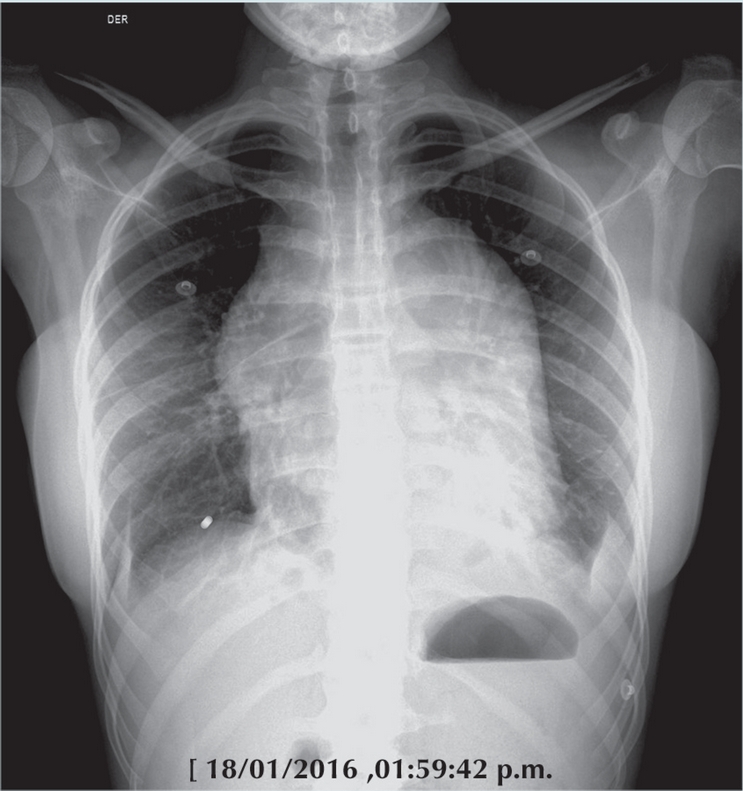

A la paciente se le realizaron estudios iniciales de la placa radiográfica de tórax (Figura 1) en la que se aprecia con masa mediastinal en mamas. Se inició abordaje radiológico con estudio de ultrasonografía pélvica y de mamas, así como tomografía computada mediastinal y abdómino pélvica donde se corrobora lesión tumoral en diversos niveles: mediastino, mamas y en pelvis a nivel parametrial, que el estudio de PET CT corroboró con un alto metabolismo de hasta 16 de SUVmax (Figura 2).

Con el tratamiento instituido, la niña entró en remisión y desparecieron la masa mediastinal y los datos de afección mamaria (Figura 5). La autopsia aclara el cuadro final con una complicación pulmonar por Toxoplasma gondii; es una complicación rara de la inmunosupresión; sin embargo, de los parásitos intracelulares es el más usual. Se describe en el paciente inmuno comprometido con opacidades nodulares gruesas o con un patrón retículo nodular grueso, difuso, como el presentado finalmente por nuestra paciente, con una progresión rápida (Figura 6).

Al momento de su ingreso, fue vista por Neurología y al considerar que se trataba de un cuadro agudo que sugería un proceso inflamatorio y objeto de manejo inmediato se transfirió al Servicio de Infectología con el diagnóstico de presunción de meningitis. Los estudios de imagen, como ya desglosó el Dr. de Uña, muy pronto esclarecieron la naturaleza del problema. La resonancia magnética reveló alteraciones en pares craneales y en médula espinal y la placa de tórax documentó la hipertrofia mamaria y mostró una gran masa en mediastino anterior y medio.